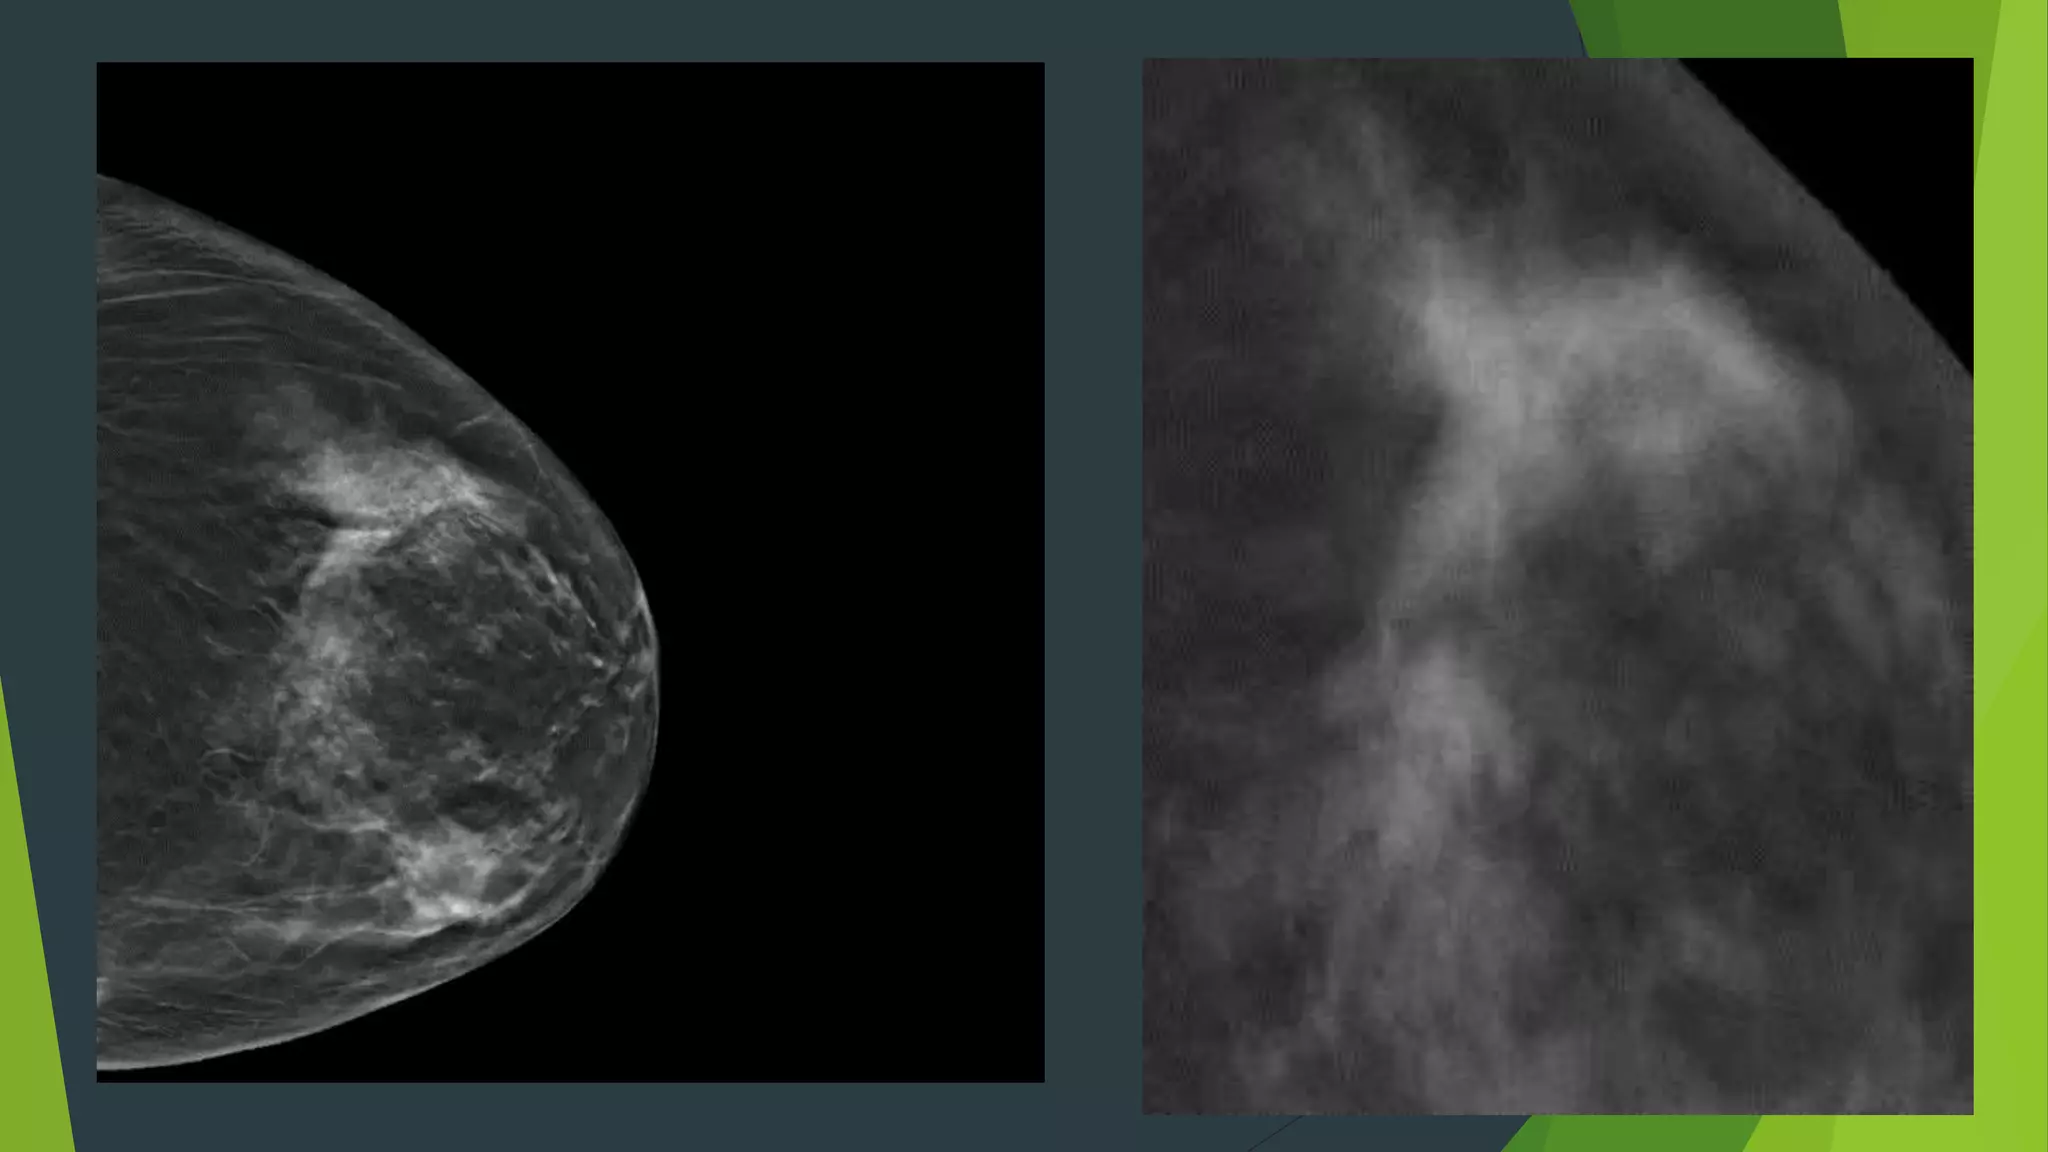

Technique:  2D and 3D images obtained with

one compression

 X-ray tube sweeps through a 15deg

arc acquiring 15 low dose

projections (~4secs)

 Mathematical reconstruction

generates 1mm slices through the

breast

 C-view (synthesized 2D)

 2D will no longer be needed

 Dose reduction

Technique:  2Dand 3D images obtained with one compression  X-ray tube sweeps through a 15deg arc acquiring 15 low dose projections (~4secs)  Mathematical reconstruction generates 1mm slices through the breast  Radiation dose: ~2X the dose of a mammogram  Still very low, below MQSA requirements  C-view (synthesized 2D)  2D will no longer be needed  Dose reduction Hologic